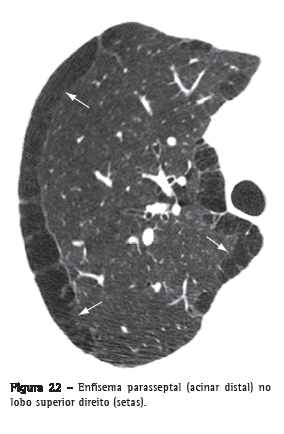

Enfisema parasseptal (acinar distal)

Enfisema que envolve predominantemente os alvéolos distais, seus ductos e sacos alveolares. Caracteristicamente, é delimitado por qualquer superfície pleural ou septos interlobulares. Na TC, caracteriza-se por áreas de baixa atenuação nas regiões subpleurais e peribroncovasculares, separadas por septo interlobular intacto (Figura 22).(37,38) Algumas vezes associa-se a bolhas.